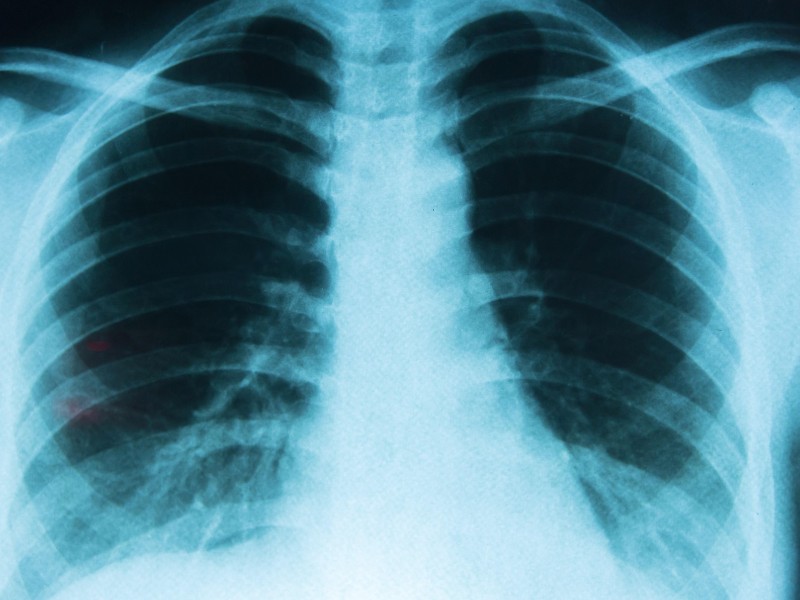

El cáncer de pulmón se presenta cuando células anormales crecen de forma descontrolada en el tejido pulmonar. Los tipos más frecuentes son el carcinoma de células no pequeñas y el carcinoma de células pequeñas. Por su impacto y el número de muertes que provoca a nivel internacional, continúa siendo uno de los problemas de salud pública más relevantes.